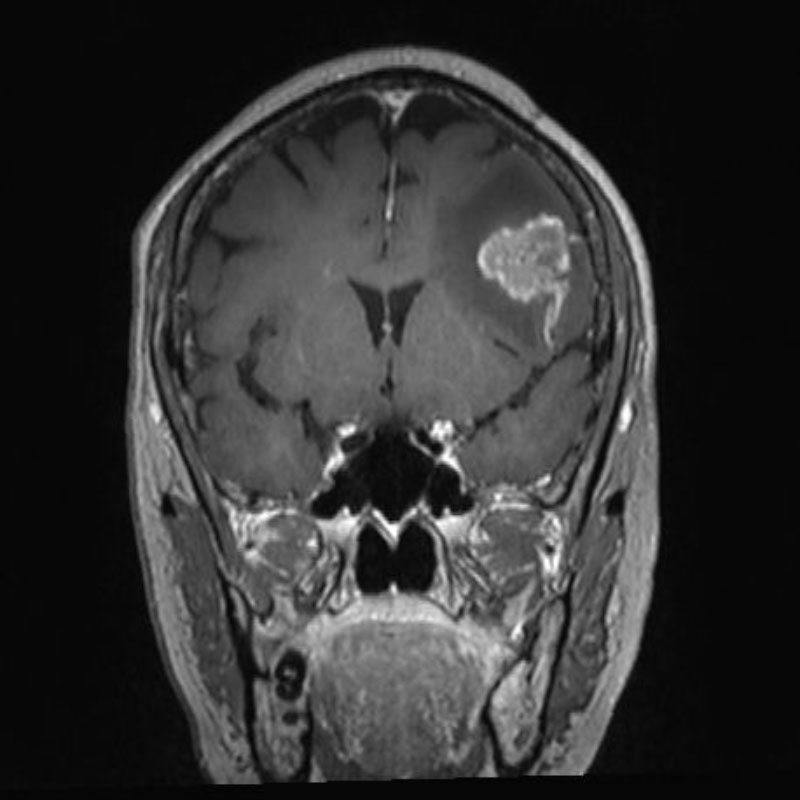

No.’25_108 手術前1

No.’25_108 手術前2